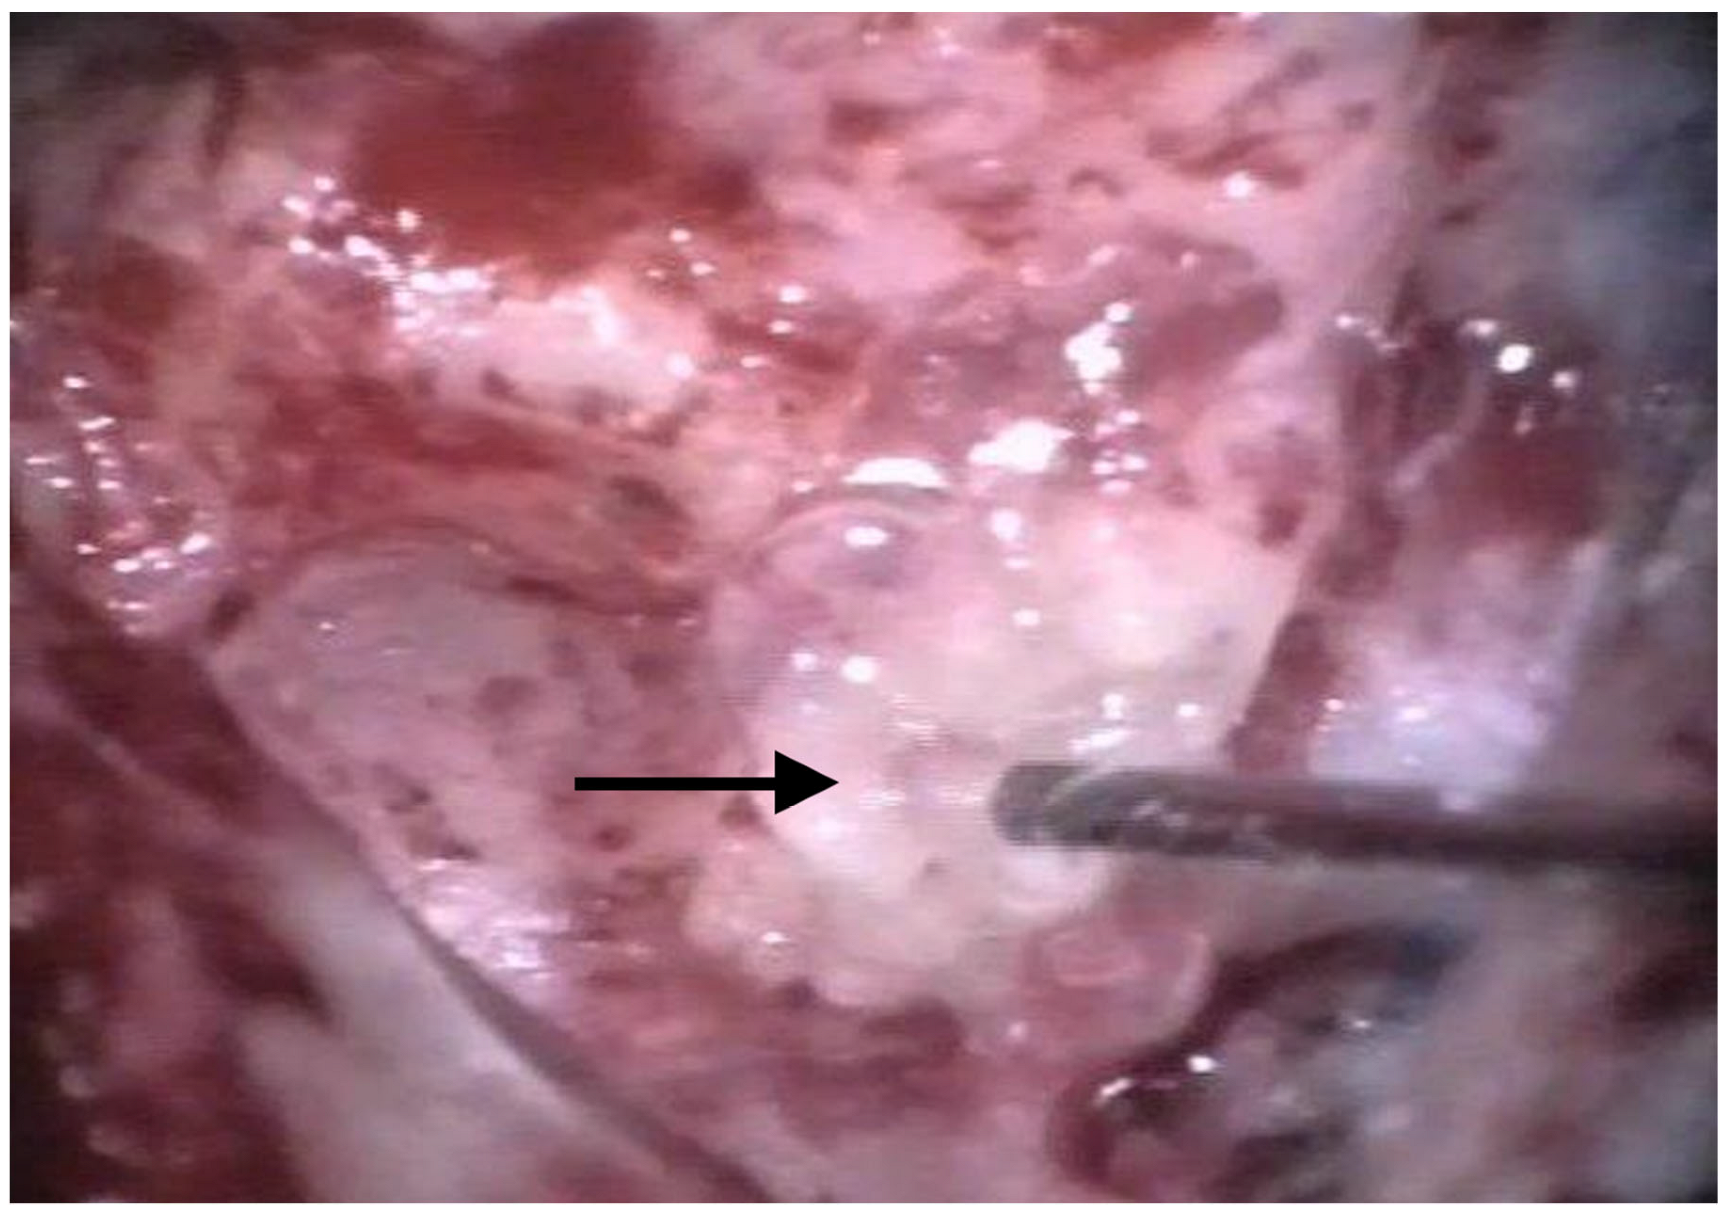

The patients were treated between August 2013 and October 2015 using the identical surgical technique of one-stage cochlear implantation and the occlusion of all three ipsilateral semi-circular canals. For cochlear implantation, a posterior tympanotomy and a round window approach were chosen [14]. Occlusion of the three semi-circular canals was performed before the implantation by reducing the drill speed to 10,000/min. The labyrinth was skeletonized to identify all semi-circular canals. The superior bony layer of the semi-circular canal was drilled down with a diamond burr (2.3 mm) until the endolymphatic duct shone through the last bony layer (blue lining) (Figure 1 and Figure 2). Leaving the endolymphatic duct intact, the temporalis fascia was pushed down in the canal. After sealing with fascia, the canal was filled with bone wax (Figure 3). The area of each canal was covered afterward with a muscle patch and bone pate. Finally, the sealing patch was secured with fibrin glue (Figure 4) [5,15].

Figure 1. Blue lining of the lateral semi-circular canal with the diamond burr. The arrow points to the lateral semi-circular canal.